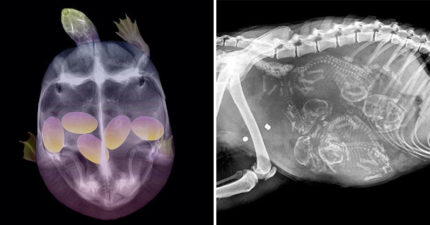

10張超稀有「動物媽媽懷孕X光照」曝光 狗媽媽肚子裡的畫面….密集恐懼注意!

October 1, 2019

世界

,

動物

圖文